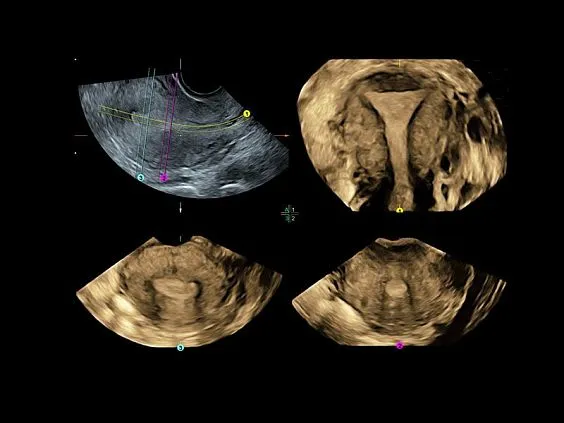

Клинические изображения

- Программа 3D и режим инверсии (при наличии специализированных датчиков).

- Программа 3D и режим инверсии (при наличии специализированных датчиков).

- Гинекология

- Advanced VCI (Volume Contrast Imaging) — расширенный программный пакет объемного контрастного изображения (VCI) для объемных датчиков:

- Проведение любой произвольной плоскости в 3D/4D (OmniView).

- Объемное контрастирование любой произвольной плоскости (OmniView+VCI).

- Регулировка толщины и формы коронарного среза в 3D/4D (получение коронарной плоскости в 3D/4D, например, для оценки мозолистого тела — автоматическая функция «Corpus Callosum»).

- Volume Calculation II (VOCAL — Virtual Organ Computer Aided Analysis) — программное обеспечение для полуавтоматического определения контуров структур и расчета их объема в режиме объемной реконструкции.

- RIC5-9-D — 4D внутриполостной датчик 4-9 МГц.